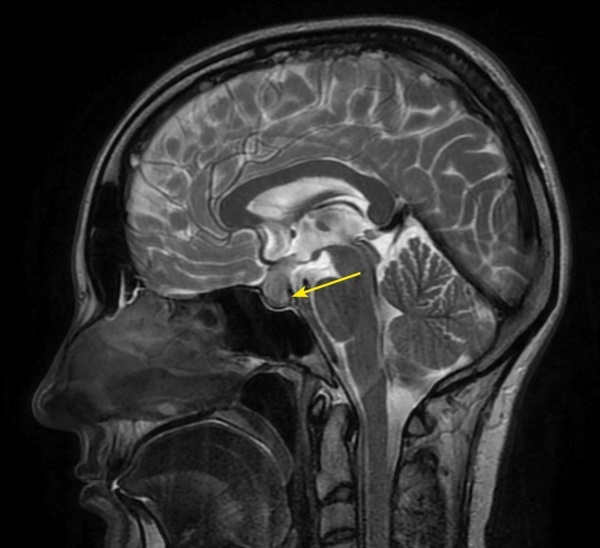

Autoimmune/lymphocytic hypophysitis is one of the rare causes of central diabetes insipidus in adults and is most common among women in the second or third trimester of pregnancy. Numerous studies have shown that lymphocytic hypophysitis is characterized by a very variable clinical signs with the development of neurological symptoms, visual disturbances and hypopituitarism with partial or complete loss of pituitary function, as well as a number of features in magnetic resonance imaging (MRI). Isolated lymphocytic indibuloneurohypophysitis occurs in fewer cases and involves the posterior lobe and stalk of the pituitary gland with a clinical presentation of diabetes insipidus. The above clinical case describes the development of hypophysitis in a pregnant woman with a predominant lesion of the posterior pituitary gland and an outcome in diabetes insipidus, which persists 6 years after pregnancy and childbirth. In the article some aspects of the differential diagnosis of diabetes insipidus in pregnant women, as well as instrumental diagnosis and treatment approaches of hypophysitis are discussed.